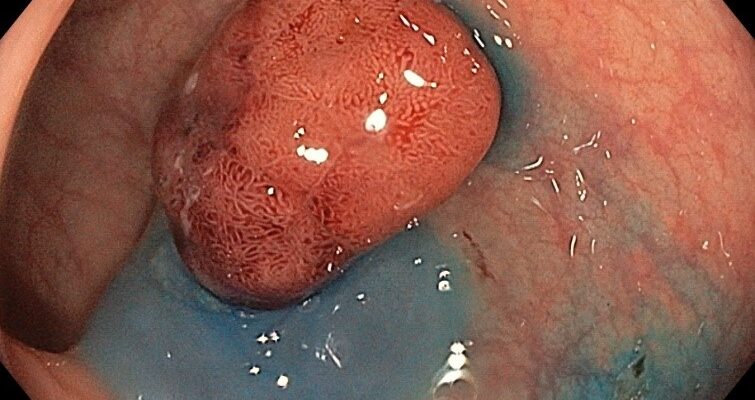

Rezecția polipilor colonici, denumită polipectomie, se realizează cel mai frecvent endoscopic, atunci când pacientul efectuează colonoscopia și sunt depistate aceste leziuni premaligne. În funcție de numărul, dimensiunea și rezultatul histopatologic ale polipilor rezecați sunt enunțate recomandările de monitorizare colonoscopică a...